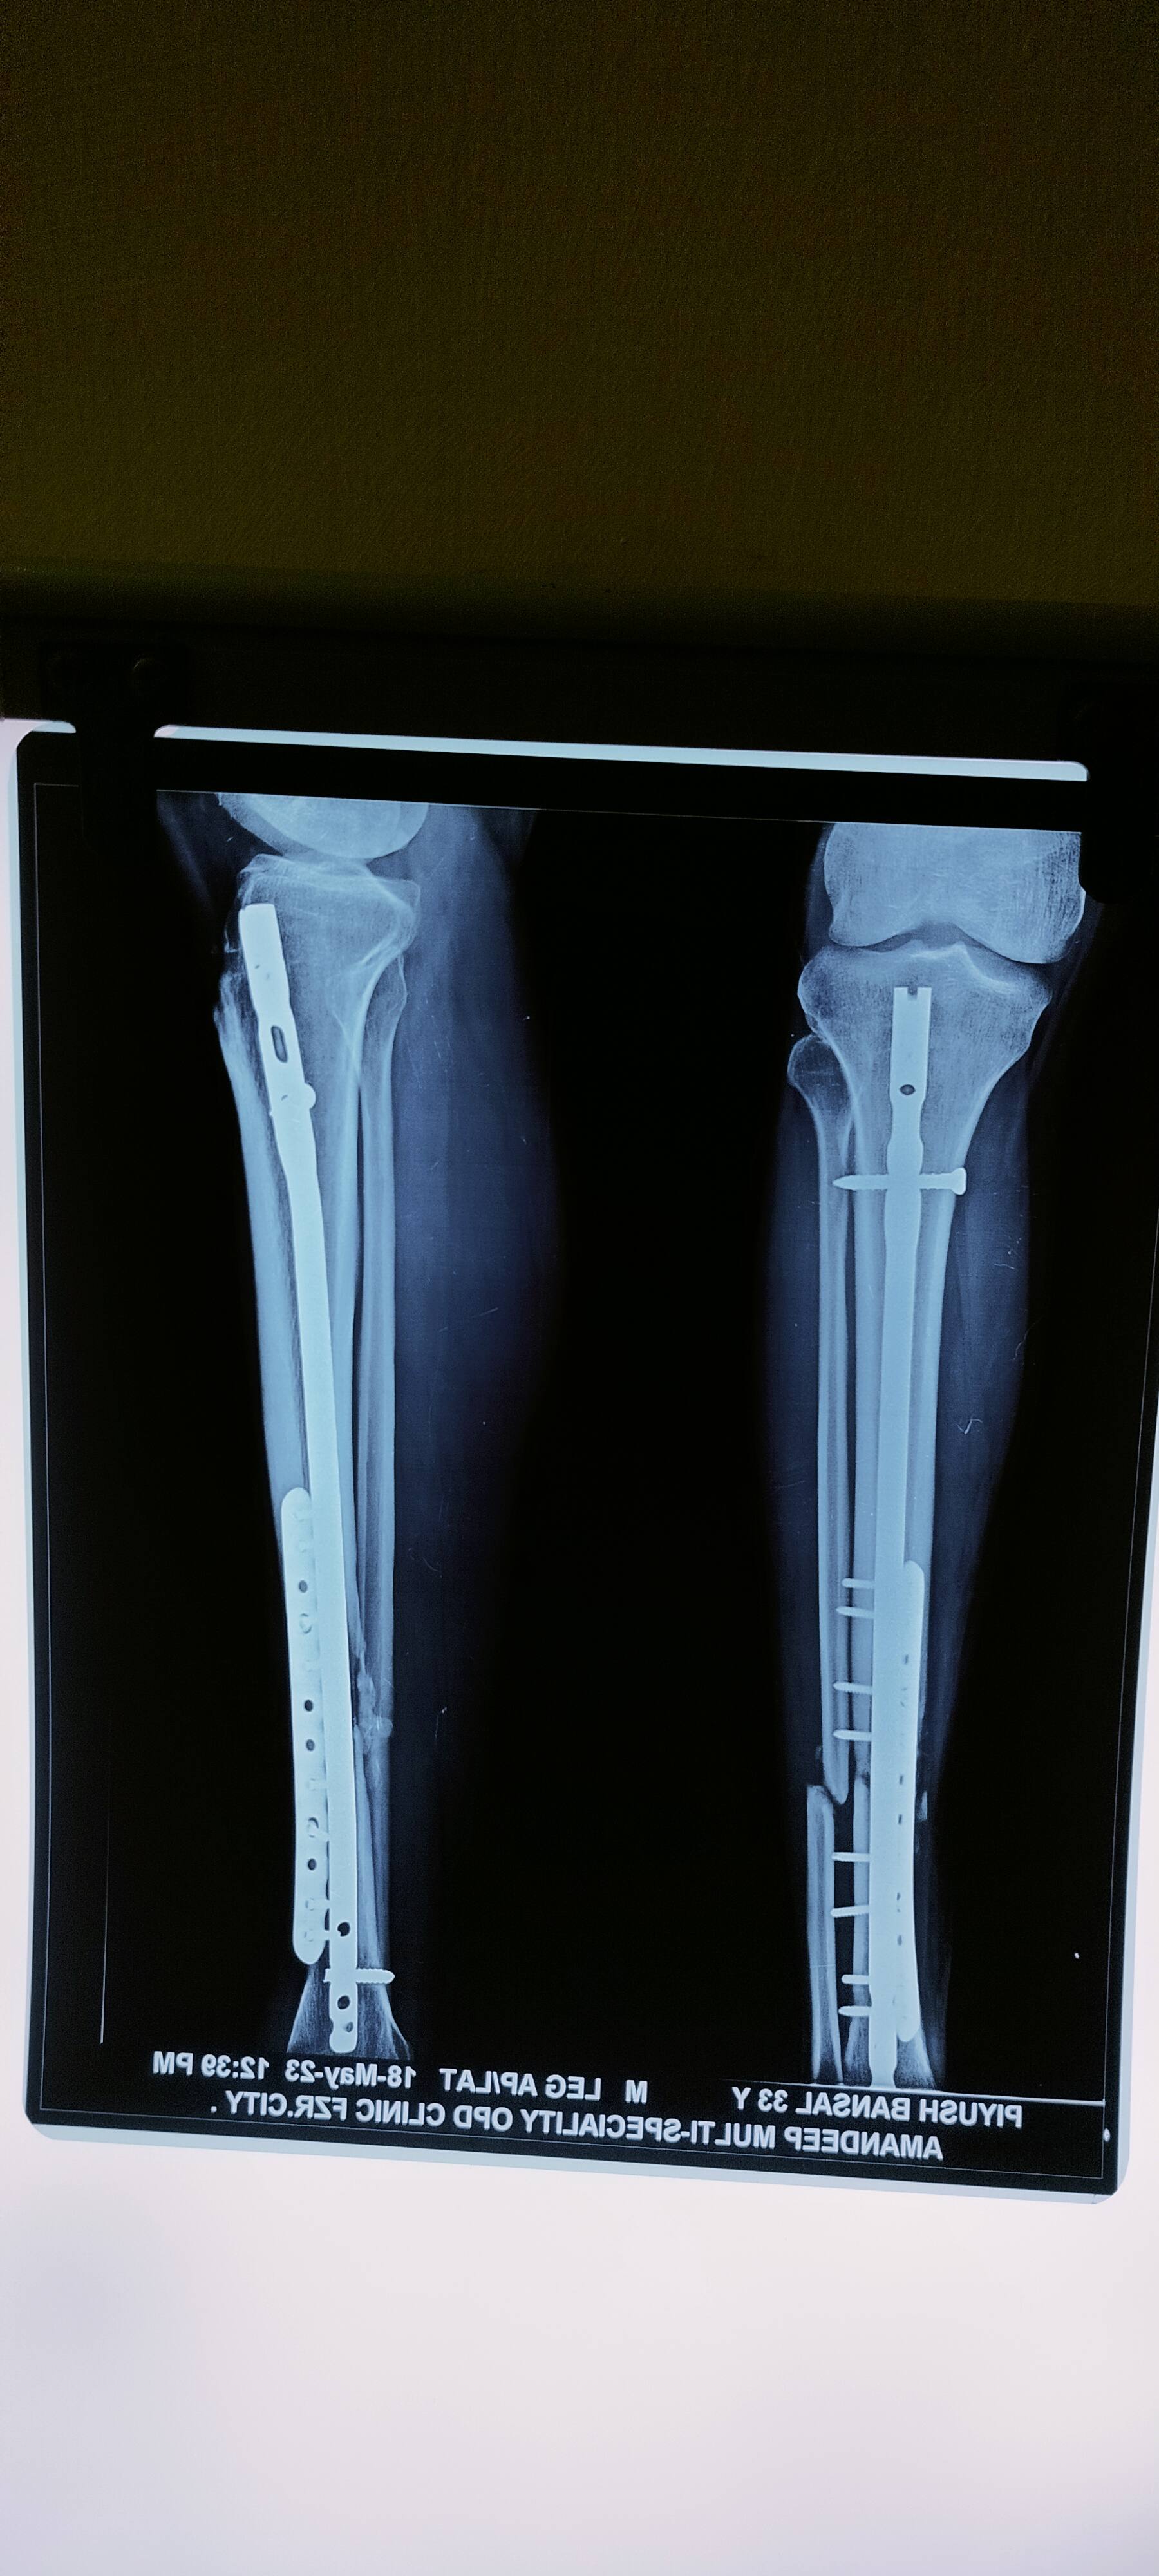

I met with an accident in 2021 n got tibia n femer bone open fractured n operated . Nailing was done at ISEC at delhi, I had to undergone resurgery bone grafting n plate implanted in March 2023. Now I want to take some suggestion from you. Kindly tell me After Gf n implant how much time it will take to recover. Is it getting recover ? Latest Xray is attached. Thank you